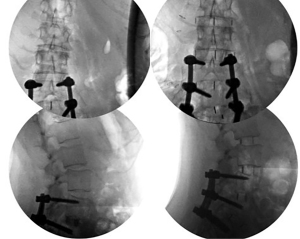

- After placing the implants in all target levels, confirmation of proper realignment and placement of instrumentation with fluoroscopy is performed.

- Upon completion of the procedure, there are two options for patient positioning. The patient can either be turned supine and extubated, or alternatively turned prone for additional fixation. The interbody fusion of the anterior spinal column can be supplemented by posterior pedicle screw fixation, creating a circumferential fusion construct. This additional posterior fixation can be performed either during the same surgical setting or in a staged manner, providing the patient with more time for recovery in between procedures. It is essential to consider the need for additional posterior fixation in cases with high biomechanical stress, such as those involving instability, sagittal imbalance, and spondylolisthesis and/or spondylolysis. By addressing these specific conditions, the surgeon can enhance the overall stability and success of the fusion procedure.